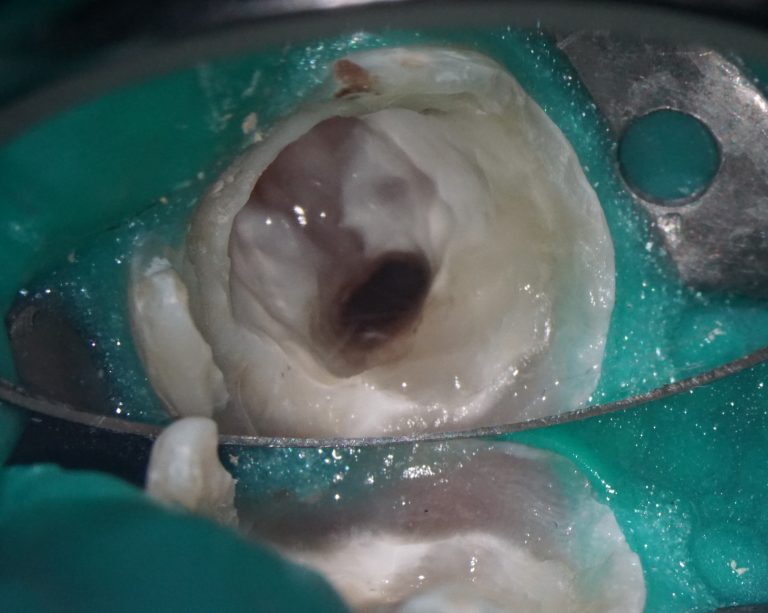

A complete diagnosis is the basis for a correct and timely treatment. In this periodontal case a patient complained of sore gums and bleeding, which had bothered her for several years.

A cross-sectional radiological report created by Diagnocat AI allows the clinician to detect a subgingival calculus and make an accurate prognosis of each tooth before starting any complex treatment, whilst taking into account all of the endodontic, periodontal and functional criteria.

Thanks to all the data gathered by Diagnocat, a plan was created which achieved a positive treatment result.